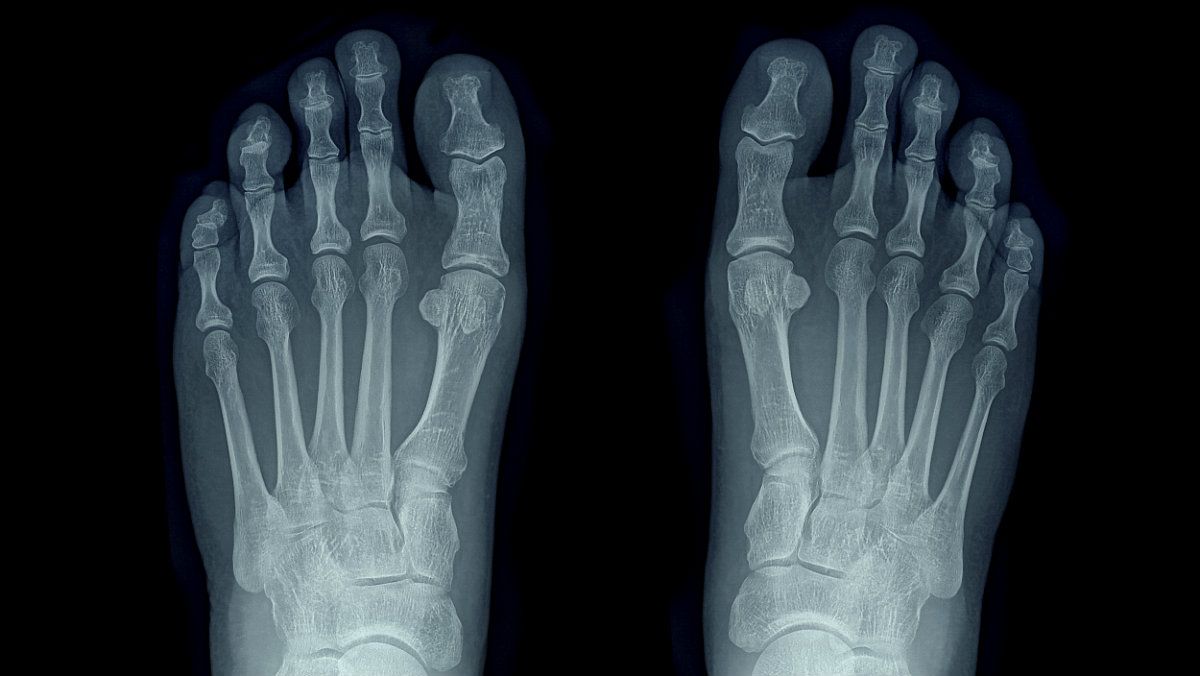

La radiología diagnóstica en directo de pie y tobillo, también conocida como fluoroscopia, es una técnica de imagen que utilizamos el equipo de podología de nuestra clínica. Utiliza radiación ionizante en tiempo real para obtener imágenes dinámicas de las estructuras óseas y articulares del pie y el tobillo. A diferencia de las radiografías convencionales, que capturan imágenes estáticas, la fluoroscopia permite visualizar en tiempo real el movimiento y la función de las articulaciones, lo que resulta útil para diagnosticar ciertas condiciones patologías y guiar procedimientos intervencionistas.

· Evaluación de las fracturas y luxaciones: Permite una evaluación en tiempo real de fracturas óseas, incluidas las fracturas articulares y las fracturas por estrés, así como la detección de luxaciones y subluxaciones articulares.

· Evaluación de la función articular: Permite la visualización en tiempo real de la función y la estabilidad de las articulaciones durante movimientos específicos, lo que ayuda en la evaluación de lesiones ligamentosas, inestabilidades articulares y enfermedades degenerativas.

· Diagnóstico de las enfermedades degenerativas: Permite la detección de cambios degenerativos en las articulaciones, como la osteoartritis, la artritis reumatoide y la gota, mediante la evaluación de la alineación articular, el espacio articular y la formación de osteofitos.